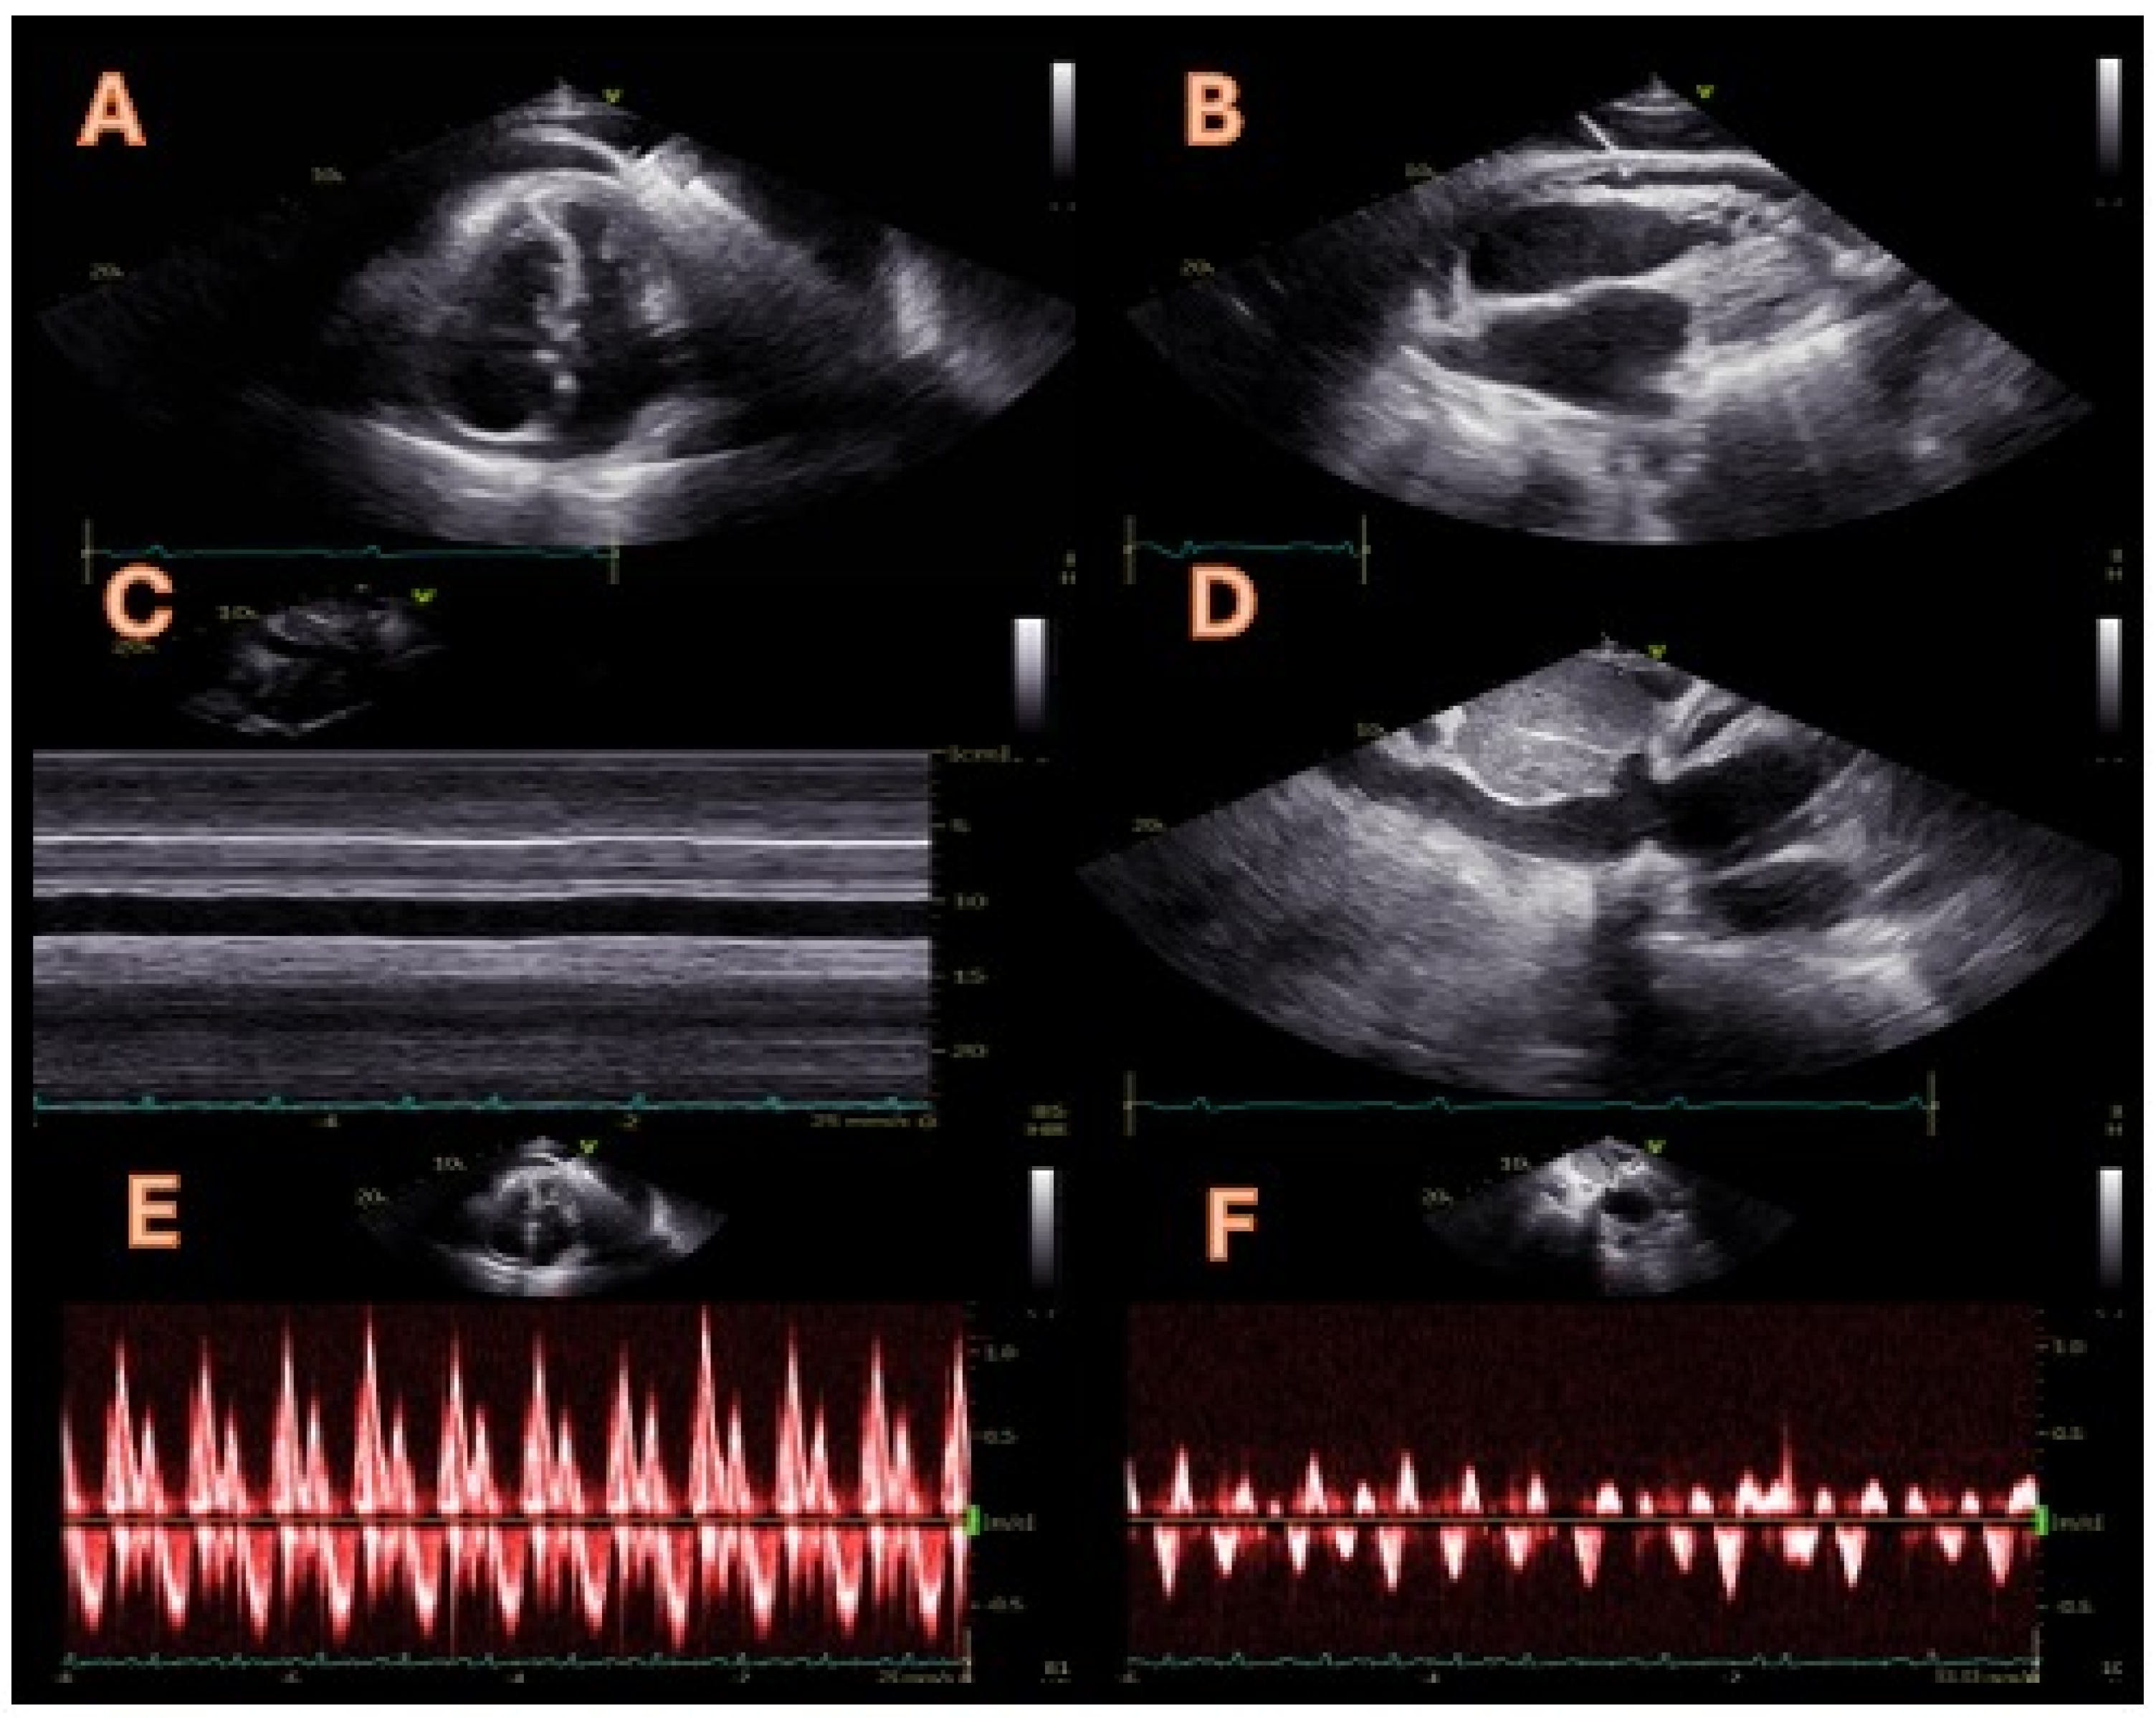

Figure 1. A 72-year-old man with a diagnosis of constrictive pericarditis was referred to our cardiology unit in April 2024 to assess his eligibility for a pericardiectomy. The previous diagnosis of constrictive pericarditis was based on symptoms of volume overload (peripheral oedema and weight gain) with typical features on a transthoracic echocardiogram (TTE). Upon admission, the TTE showed paradoxical motion of the interventricular septum during early diastole (septal bounce, panel (A)) and moderate pericardial effusion (panel (B)). Septal bounce is an echocardiographic sign of ventricular interdependence, serving as one of the diagnostic criteria for constrictive pericarditis identified by the Mayo Clinic [1]. Additionally, both bidimensional and M-mode assessments showed a dilated inferior vena cava that exhibited no motion during spontaneous breathing or forced inspiration (sniff), as illustrated in panels (C,D). These observations indicate inferior vena cava plethora, which may also occur in volume overload conditions or cardiac tamponade; therefore, if present, it is not included in the Mayo Clinic’s diagnostic criteria due to its low specificity and sensitivity. Lastly, a pulsed Doppler evaluation of mitral flow displayed a decline in the peak mitral E-wave velocity of over 25% during the initial inspiration alongside a prolonged isovolumic relaxation time (panel (E)). Meanwhile, a pulsed Doppler assessment of the hepatic veins revealed a characteristic W-shaped pattern, indicating significant diastolic flow reversals during the expiration and dilation of the hepatic veins (panel (F)). These last two observations are characteristic of constrictive pericarditis and confirm the diagnosis for this patient in conjunction with the abnormal septal movement.

Diagnostics 14 02642 g001